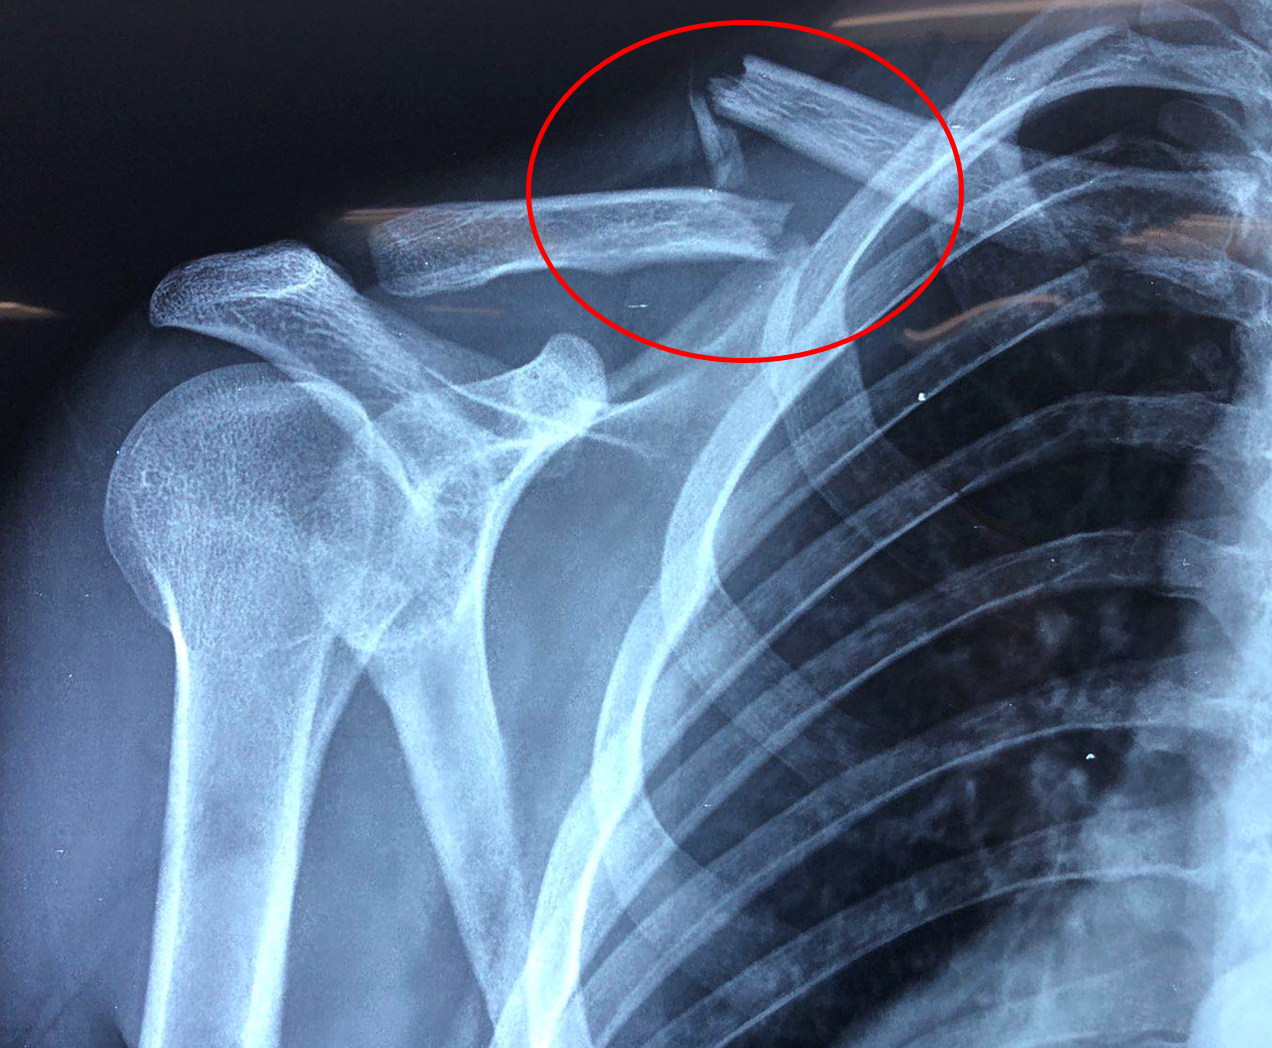

Κάταγμα Κλείδας

Πρόκειται για ένα κάταγμα του οστού της κλείδας, η οποία συνδέει τον κορμό με το άνω άκρο. Το κάταγμα αυτό είναι αρκετά συχνό και προκαλείται συνήθως μετά από τραυματισμό, όπως για παράδειγμα μια πτώση ή ένα τροχαίο ατύχημα.

Διάγνωση

Ο ασθενής με κάταγμα κλείδας χρειάζεται εκτίμηση από εξειδικευμένο Ορθοπαιδικό Χειρουργό. Ο κ. Βλάχος θα λάβει το ιστορικό σας και θα σας εξετάσει πολύ προσεκτικά. Επίσης θα χρειαστεί η λήψη μιας ακτινογραφίας και σε συγκεκριμένες περιπτώσεις ο ιατρός

θα σας παραπέμψει για αξονική τομογραφία.